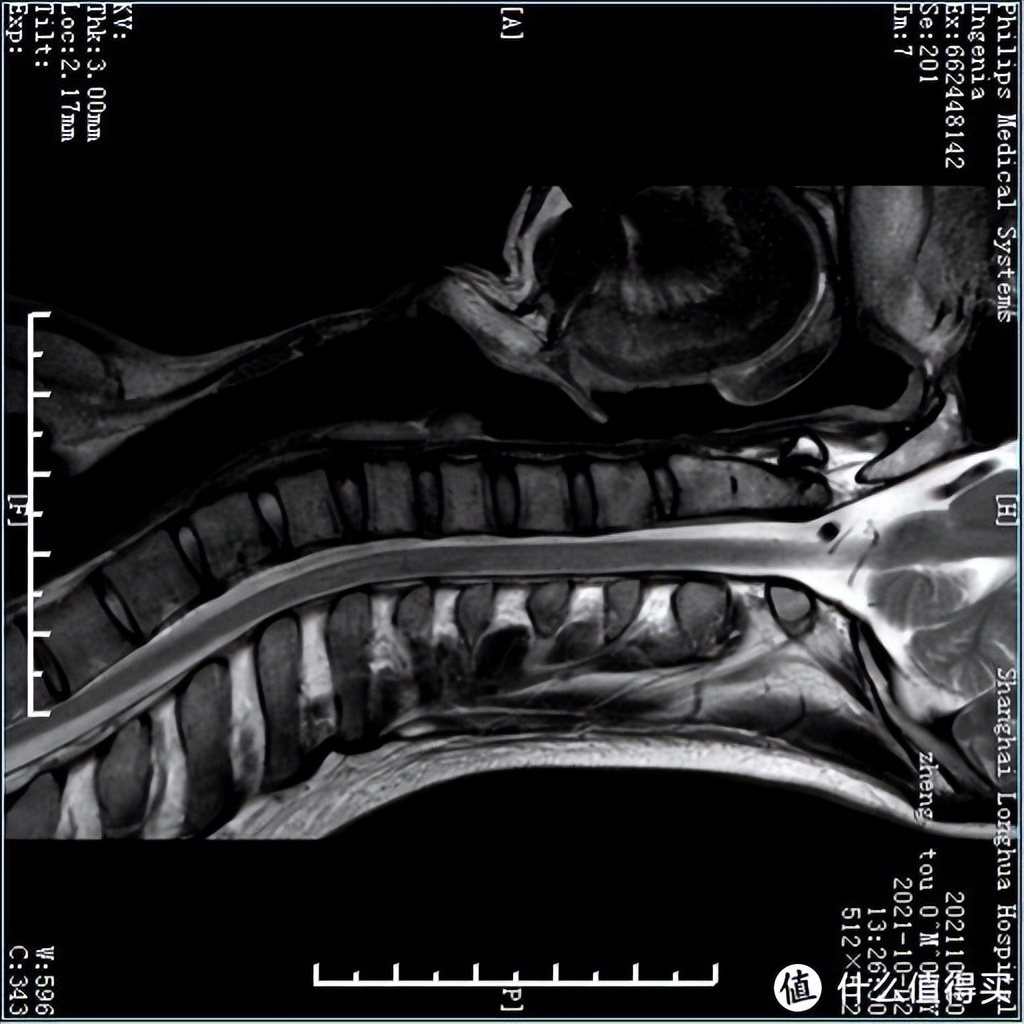

为了看到枕着不同枕头的状态下,颈椎内部结构会怎么改变,我还特意来到放射科,麻烦值班的兄弟给做了16组MRI成像。也感谢志愿者的付出。

首先让志愿者用仰卧位和侧卧位,无枕头的状态下拍摄了颈椎MRI,为了让人看明白,我特意把颈椎横过来摆到正常睡姿的体位。

仰卧位颈椎MRI: 不枕枕头的情况下,因为MRI机器本身有个固定器,头部还是处于比较合适的中立位,志愿者的上颈段椎间盘出现一定程度的退变,曲度略微反曲

侧卧位颈椎MRI: 为了看到侧卧的颈椎结构,我们用了一些小技巧,让机器略微识别出来了大致轮廓,尽管如此,下侧边缘还是有些模糊。但可看到侧卧位,因为没有枕头,头部往下掉,颈椎处于左右失衡的状态。

各种枕头下的MRI详细解读,我会专门出一期视频,现在还没有剪辑好,大家感兴趣的话可以点个收藏,点个追更,这两周就会有重磅测评结果发布~